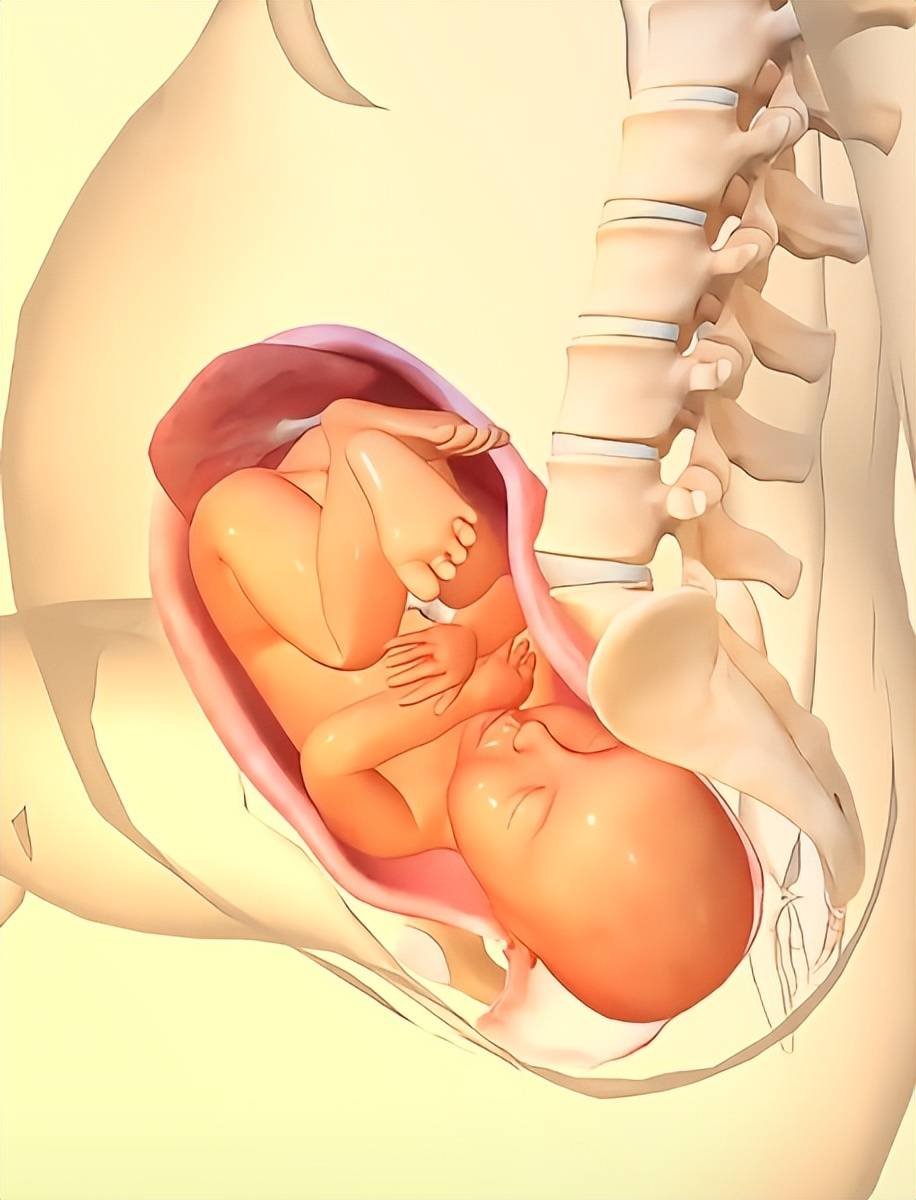

孕期